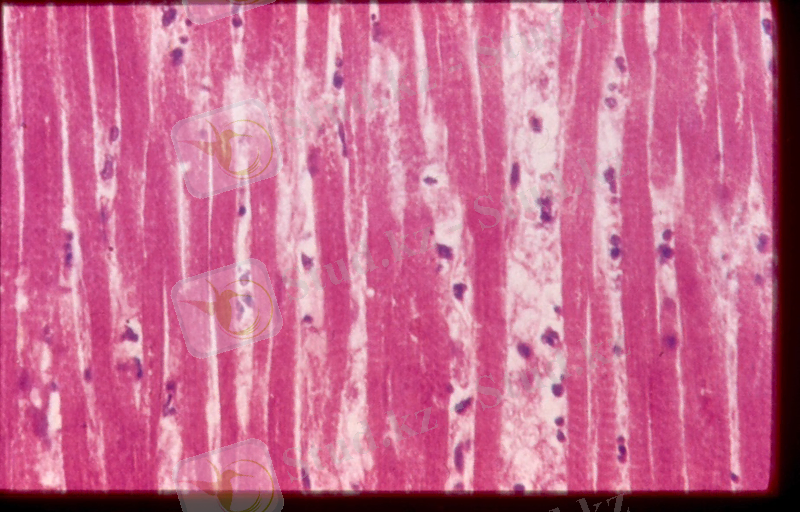

2 сурет. Бүйректегі ақ инфаркт микроскопиялық көрінісі

- Қызыл инфаркт- некроз зонасы қара - қызыл қанмен сіңген. Бұл тип өкпеде, бас миында байқалады. Оның дамуы венозды тоқырау және органның қанмен қамтамасыз етуі нәтижесінде. Венозды тоқырау айқындалмаған деңгейінде геморрагиялық инфаркт тудыруы мүмкін. Геморрагиялық инфаркттың негізгі формасы веноздық инфаркт болып саналады, соның себептері окклязия болып табылады. Қызыл инфарктіні микроскоппен коргенде мүшенің қалыпты құрылымы жойылған, қанмен лық толған ұсақ қантамырынан тыс жерде быжынағанэритроциттер көрінеді. Венада қанның іркіліп ағуы мұндай инфарктке әкеліп соғатын қолайлы жағдай. Әдетте қызыл инфаркт ішекте, өкпеде, талақта кейде бүйректе де кездеседі.

4 сурет. Қызыл инфаркттың микроскопиялық көрінісі